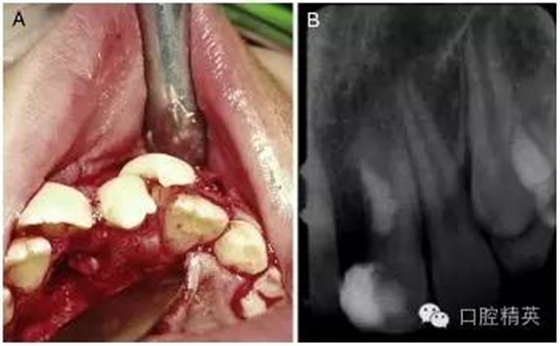

手術(shù)在局麻下進(jìn)行,無術(shù)前用藥,也沒有對(duì)口腔進(jìn)行其他特殊的術(shù)前準(zhǔn)備。為了分牙的便利,患牙唇頰側(cè)的牙齦黏膜都被切至骨膜進(jìn)行了徹底的翻瓣(圖 2-A)。

為了劈開牙冠和部分牙根,一把鋒利的骨鑿被順著牙長(zhǎng)軸方向并稍向遠(yuǎn)中傾斜地放置在了融合牙切端的發(fā)育溝中。在錘子的猛擊下,這顆過大牙齒的多生部分被逐漸劈離出來。按照術(shù)前計(jì)劃,并通過術(shù)中調(diào)整骨鑿的傾斜度,分離的剖面最終被止于齦下。

分牙過程中,在牙根中 1/3 處出現(xiàn)了一個(gè) 4mm 范圍的橢圓形的洞,通過洞可以觀察到暴露的牙髓。牙體牙髓醫(yī)生立即用 MTA 和調(diào)拌刀對(duì)這個(gè)洞進(jìn)行了修補(bǔ)和拋光(圖 2-B)。翻瓣縫合之前,口腔外科醫(yī)生對(duì)尖銳的骨刺進(jìn)行了修整,以便縫合后的牙齦黏膜能夠與硬組織緊密地貼合在一起。

圖 2 手術(shù)過程。(A)為了方便劈牙,對(duì)唇腭側(cè)牙齦黏膜做了徹底的翻瓣。(B)多生牙部分劈開拔除后和 MTA 蓋髓后的 x 線根尖片。